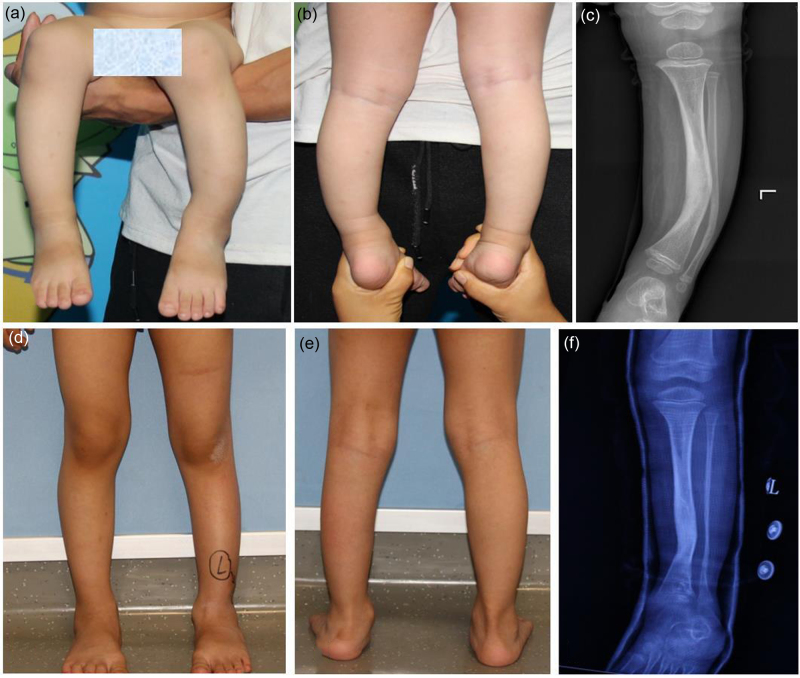

本研究的目的是探讨引导生长技术治疗儿童先天性胫骨前外侧弯曲(ALBT)的早期有效性。对2020年1月至2022年10月在两个中心接受“U”型钉引导生长技术治疗的18例ALBT患者进行回顾性分析。术前、取出植入物时或最后一次随访时采集双下肢、胫骨和腓骨的正侧位x线片。统计分析胫骨干骺端冠状角、矢状角、胫骨内侧近端解剖角(aMPTA)和胫骨外侧远端解剖角(alta)的变化,评价ALBT的矫正效果。所有患者平均随访23.36个月(14.53 ~ 37.2个月)。18例患者均表现出冠状面胫骨轴角的改善,平均矫正17.94°(范围:5.54°-33.52°)。14例患者矢状面胫骨轴角改善,平均矫正13.44°(范围:1.89°-32.6°)。治疗后aMPTA和alta水平均下降。随访期间,18例患者均未发生胫骨假关节。引导生长技术可以有效地改善ALBT,防止胫骨进一步的角度畸形,并可能延迟或预防胫骨假关节。此外,引导生长技术操作简单,微创,并发症少。

The aim of this study was to investigate the early effectiveness of guided growth techniques for managing congenital anterolateral bowing of the tibia (ALBT) in children. A retrospective analysis was performed involving 18 patients with ALBT treated with the 'U'-shaped staple-guided growth technique between January 2020 and October 2022 at two centres. Anteroposterior and lateral radiographs of both lower limbs and the tibia as well as the fibula were collected before surgery, at the time of implant removal, or at the last follow-up. Changes in the coronal tibial diaphyseal angulation, sagittal tibial diaphyseal angulation, anatomical medial proximal tibial angle (aMPTA) and anatomical lateral distal tibial angle (aLDTA) were statistically analysed to evaluate the correction effect of the ALBT. All patients were followed up for an average of 23.36 months (range: 14.53-37.2 months). All 18 patients demonstrated an improvement in the coronal plane tibial shaft angle, with an average correction of 17.94° (range: 5.54°-33.52°). Fourteen patients displayed an improvement in the sagittal plane tibial shaft angle, with an average correction of 13.44° (range: 1.89°-32.6°). Both the aMPTA and aLDTA levels decreased after treatment. No tibial pseudarthrosis occurred in any of the 18 patients during the follow-up. The guided growth technique is effective in improving the ALBT, preventing further angular deformities of the tibia, and may delay or prevent tibial pseudarthrosis. Moreover, the guided growth technique is simple to perform, minimally invasive and associated with few complications.